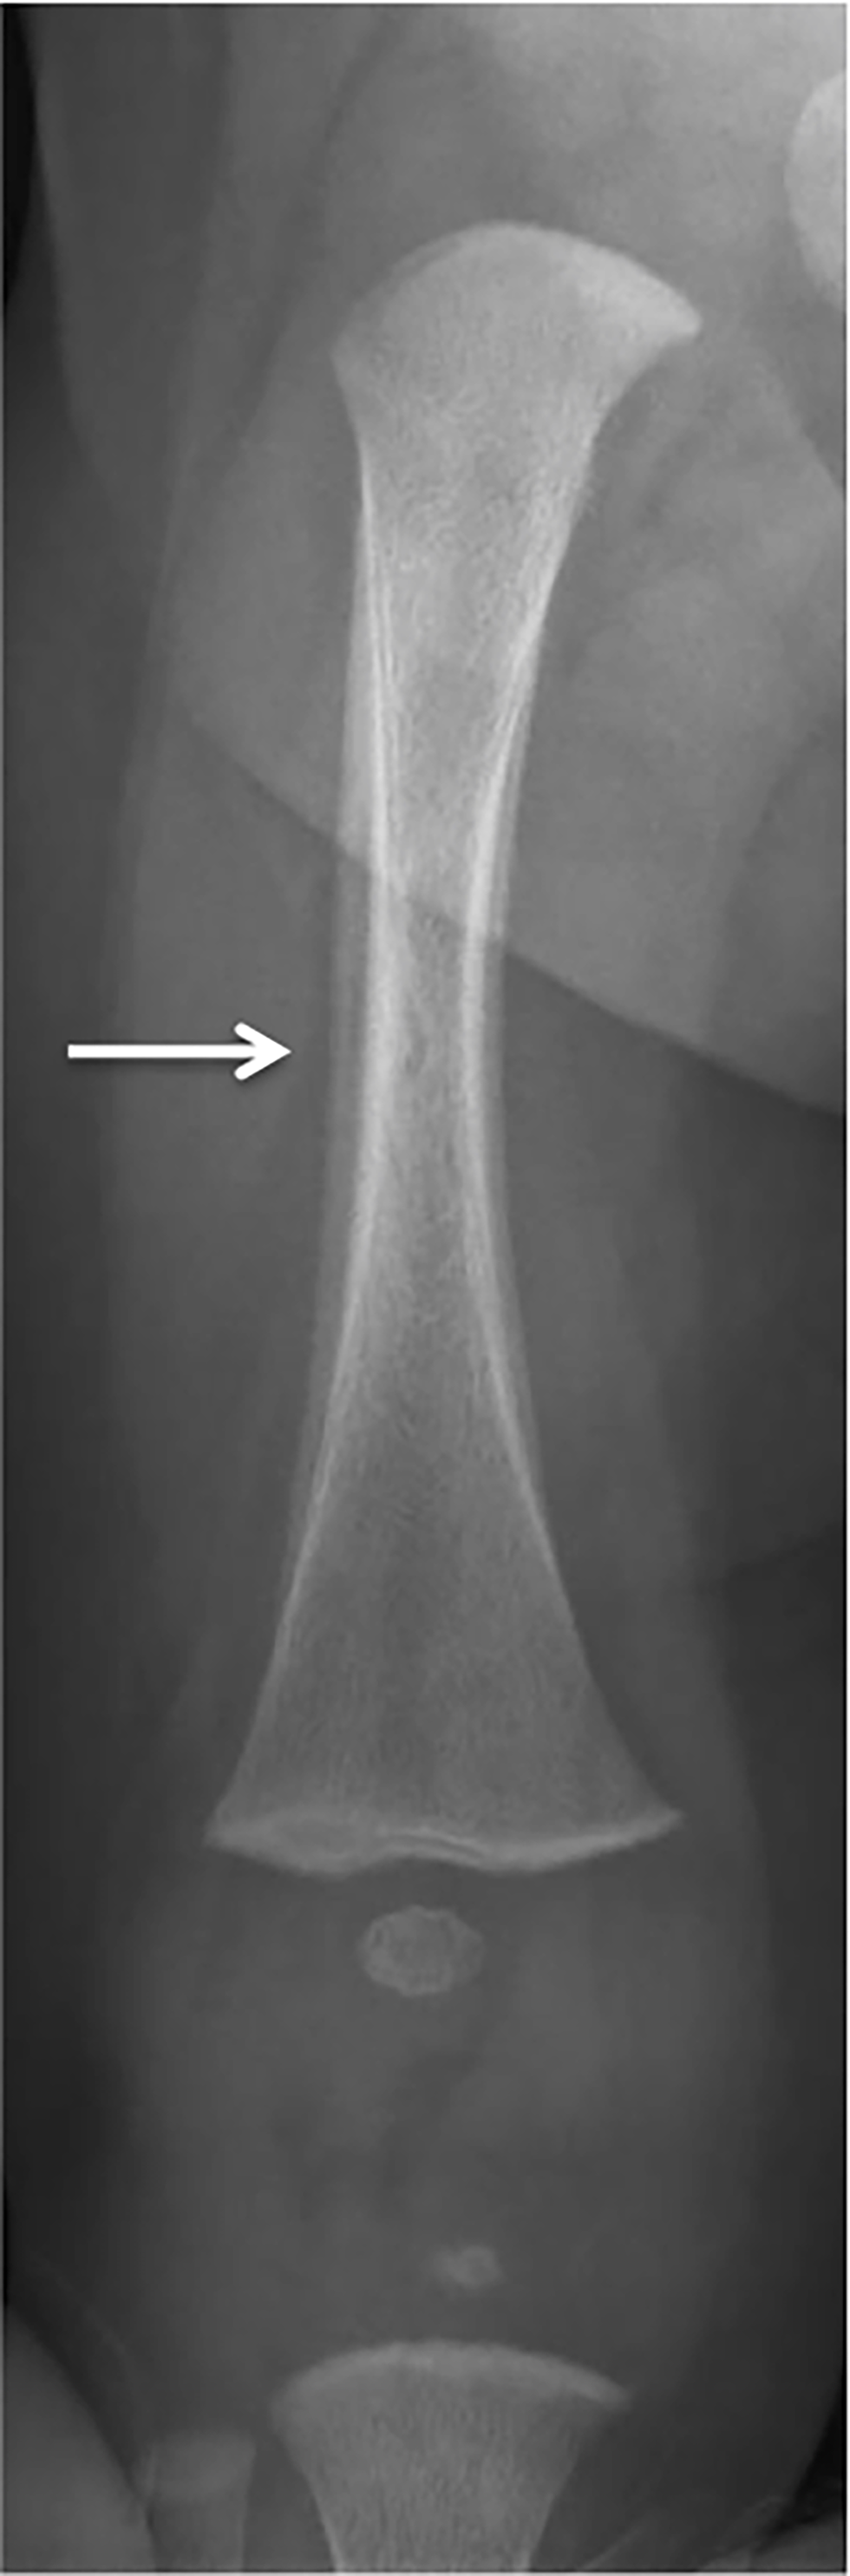

Figure 2: Radiograph of the right femurFigure 2 Footnote a of an infant with congenital syphilis, Montréal, 2021

Text description: Figure 2

A skeletal survey performed at 68 days of life showed periosteal reactions along both femurs, as well as the right tibia, that were more than physiologic for the patient’s age. No bone destruction was seen, but the zones of provisional calcification were dense.

After 10 days in hospital, the infant developed a new onset low grade fever. Given the persistent unexplained anemia, a bone marrow aspirate was planned. On repeat questioning of the mother alone for possible infectious symptoms, she described for the first-time flu-like symptoms following delivery, as well as a sore throat and genital lesions. In addition, she presented at the time of repeat questioning a bilateral erythematous scaling papular palmar rash (Figure 1) on physical examination, which had appeared in the previous three weeks. Syphilis serologies were immediately ordered on the patient and his mother. They both had strongly-positive syphilis enzyme immunoassays and rapid plasma reagin of 1:64. A lumbar puncture was performed on the infant, with the cerebrospinal fluid analysis showing normal white and red blood cell counts, glucose and protein profiles as well as a negative Venereal Disease Research Laboratory test. A cerebral magnetic resonance imaging was repeated and was normal. A skeletal survey was not conclusive for congenital syphilis, but slightly enhanced periosteal reactions were noted along both femurs and the right tibia (Figure 2). Placental examination showed only one area of villitis of unknown significance, and no spirochetes were seen on immunochemistry stains.